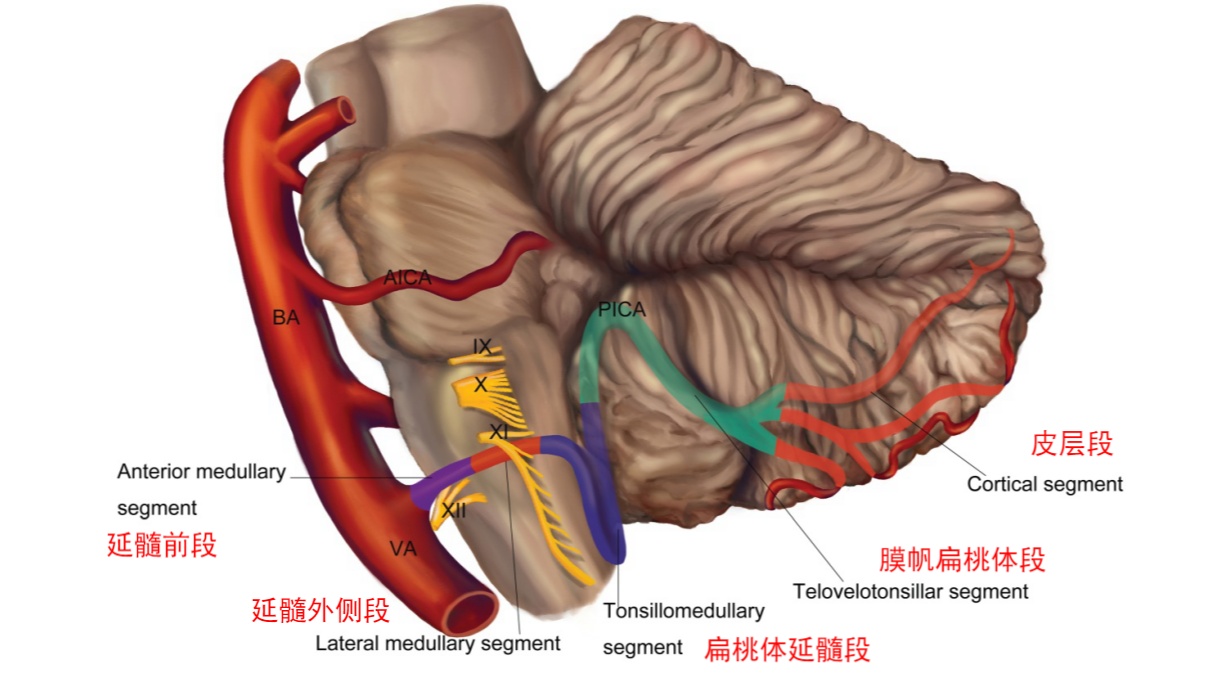

图1 小脑后下动脉分段(外侧面观示意图)。小脑后下动脉发自于椎动脉V4段,共分为5段,分别为延髓前段、延髓外侧段、扁桃体延髓段、膜帆扁桃体段和皮层段。延髓前段和延髓外侧段的分界点为橄榄最高点;延髓外侧段和扁桃体延髓段的分界点为舌咽神经、迷走神经和副神经的连线;扁桃体延髓段和膜帆扁桃体段的分界点为脉络带(四脑室下界);膜帆扁桃体段与皮层段的分界为小脑后下动脉离开扁桃体、蚓部和小脑半球之间裂隙处。扁桃体延髓段形成朝向尾部的尾襻,膜帆扁桃体段形成朝向头端的颅襻。皮层段分为内侧干和外侧干,内侧干向小脑蚓部,外侧干供应小脑半球枕下面及小脑扁桃体。